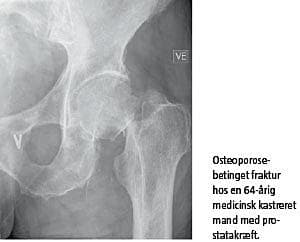

Knogleomsætningen er påvirkelig af hormon-niveauet. Hos mænd omdannes testosteron i nogen grad til det kvindelige kønshormon østrogen, og når man fjerner testosteron, mister man således positive effekter af både testosteron og østrogen på knoglerne. Man har i undersøgelser påvist, at kastrationsbehandlingen medfører et tab af knoglemasse på 2-9% det første år [1], og i de efterfølgende år er tabet af knoglemassen ligeledes forhøjet. Konsekven-serne er, at kastrationsbehandlingen medfører en øget risiko for knogleskørhed og knoglebrud. I en dansk registeropgørelse fra 2007 med data for mere end 63.000 mænd, hvoraf 1.000 havde prostatakræft, var det at have prostatakræft knyttet til næsten en fordobling af risikoen for knoglebrud [2]. Desuden viste undersøgelsen, at kastrationsbehandling medførte en yderligere forøgelse i risikoen for knoglebrud. I en anden undersøgelse fra 2005 med 50.000 mænd, som alle havde prostatakræft, så man efter fem år, at 19% af dem, som blev behandlet med kastration, havde haft et knoglebrud, mens kun 13% af dem, som ikke var blevet kastreret, havde haft et knoglebrud [3]. I flere undersøgelser har man tillige påvist en sammenhæng mellem knoglebrud og øget dødelighed, og i enkelte studier har man fundet en sammenhæng mellem prostatakræft, knoglebrud og øget dødelighed. Vi har i vores gruppe fulgt 105 mænd med prostatakræft. Vi fandt, at 10% havde osteoporose før kastrationen, og to år efter kastration var denne andel mere end fordoblet.